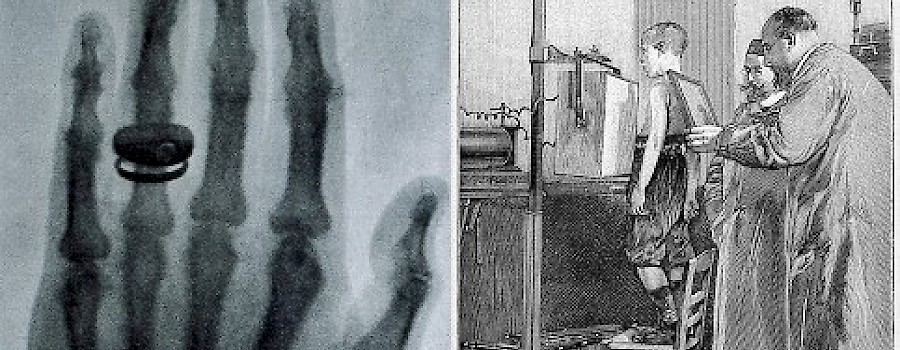

Ein grünlicher Schimmer erleuchtet den Raum. Blitze schlagen aus der altertümlich aussehenden Apparatur. Es knackt laut, und es riecht stechend nach Ozon und die Strahlenbelastung war rund 1500 Mal höher als heute.